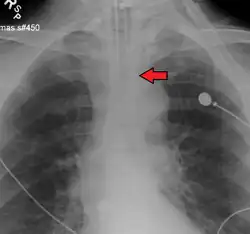

An endotracheal tube in good position on CXR. Arrow marks the tip.

An endotracheal tube not deep enough. Arrow marks the tip.

No single method for confirming tracheal tube placement has been shown to be 100% reliable. Accordingly, the use of multiple methods for confirmation of correct tube placement is now widely considered to be the standard of care.[34] Such methods include direct visualization as the tip of the tube passes through the glottis, or indirect visualization of the tracheal tube within the trachea using a device such as a bronchoscope. With a properly positioned tracheal tube, equal bilateral breath sounds will be heard upon listening to the chest with a stethoscope, and no sound upon listening to the area over the stomach. Equal bilateral rise and fall of the chest wall will be evident with ventilatory excursions. A small amount of water vapor will also be evident within the lumen of the tube with each exhalation and there will be no gastric contents in the tracheal tube at any time.[33]

Ideally, at least one of the methods utilized for confirming tracheal tube placement will be a measuring instrument. Waveform capnography has emerged as the gold standard for the confirmation of tube placement within the trachea. Other methods relying on instruments include the use of a colorimetric end-tidal carbon dioxide detector, a self-inflating esophageal bulb, or an esophageal detection device.[35] The distal tip of a properly positioned tracheal tube will be located in the mid-trachea, roughly 2 cm (1 in) above the bifurcation of the carina; this can be confirmed by chest x-ray. If it is inserted too far into the trachea (beyond the carina), the tip of the tracheal tube is likely to be within the right main bronchus—a situation often referred to as a "right mainstem intubation". In this situation, the left lung may be unable to participate in ventilation, which can lead to decreased oxygen content due to ventilation/perfusion mismatch.[36]